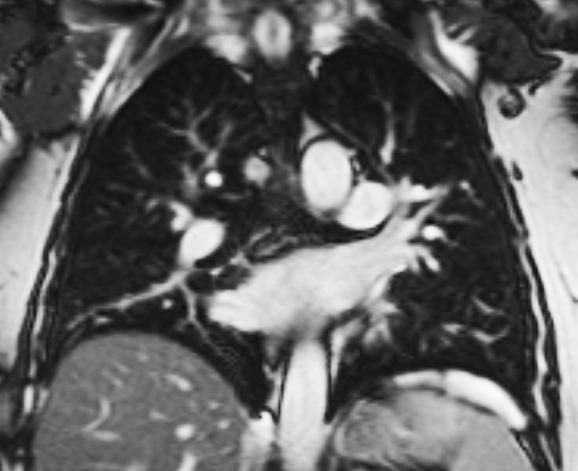

These MRI scans will help the research team evaluate the amount of air getting to different parts of the lungs and the blood supply to the lungs in healthy people and then compare these values with those found in patients. The aim eventually is to develop a way of monitoring lung disease progression in patients without requiring the use of CT scans or X-rays (which carry dangers from repeated radiation exposure).